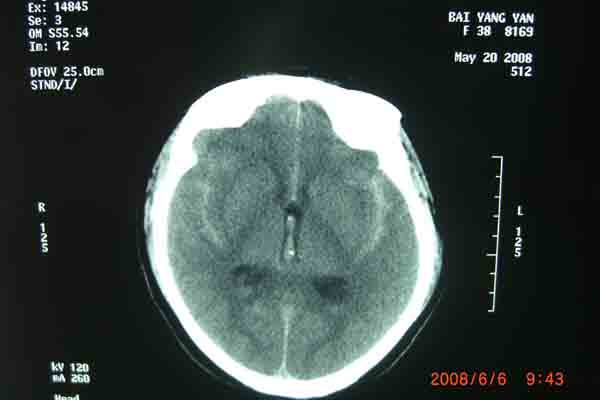

6月6日上午,在明州医院放射科的DSA检查室内。上海的神经外科专家及麻醉科在为一位38岁的云南来宁波打工中年女病人做颅内动脉瘤(眼颈交界处7*3.5cm)血管内栓塞手术。无影灯下,准备工作在有条不紊地进行着。全身麻醉后。介入手术开始了,手术医生以非常娴熟的手法,在右侧股动脉内置入导管,在显像下,随着导丝进入,顺利到达动脉瘤瘤腔内。随着弹簧圈进入,瘤腔内被充填。造影后,显示位置良好。所有的神经外科医生知道,在手术过程中,如果发生动脉瘤破裂,那后果不堪设想。手术成功了,大家悬着的心放下了。整个手术时间仅仅用了1个半小时。手术后,病人即清醒,送回病房。

回想这个病人是5月 20 日,因为在早晨起床后,突然昏迷不醒,跌到在地,被家人送往明州医院急症室,经过医生检查,这个病人已经瞳孔放大,呼吸停止。紧急地插入气管导管后,给予呼吸机使用。经过医院上海神经外科专家检查病人后,指出这是动脉瘤破裂出血导致的呼吸压制。需要头颅CT检查,在捏着皮球保持呼吸道通畅,即刻行头颅CT检查,确认为动脉瘤破裂出血,前交通动脉瘤破裂为主。专家看了片子后,认为如果行双侧脑室外引流,将血液引出,可能会使呼吸恢复。马上送手术室做急症手术,引流出血性脑脊液后,病人呼吸慢慢恢复了。经过3个星期的正规治疗(高血压,高颅压,高体温)(抗血管痉挛,抗感染)(外引流)病人终于度过了危险期。在6月6日上午成功进行了颅内动脉瘤血管内栓塞手术。